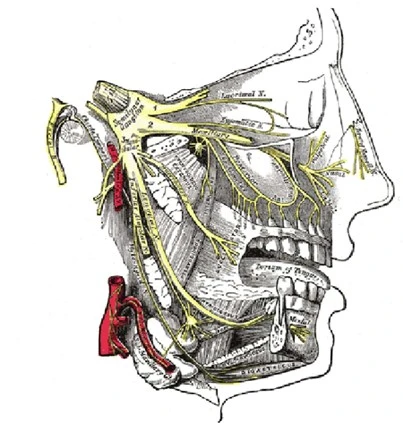

삼차신경통은 안면부 특정 영역에 발작적이고

찌르는 듯한 통증을 일으키는 신경병증이에요.

문제는 이게 치통과 증상이 너무 비슷하다는 거예요;;

✅ 우측 또는 좌측 안면부에 국한된 통증

✅ 전기 오듯 찌릿하고 예리한 양상

✅ 몇 초에서 몇 분간 지속되는 발작적 통증

✅ 씹거나 말할 때, 세수할 때 통증 유발

✅ 치과 치료로 호전되지 않음

이런 특징들이 있다면 삼차신경통을 의심해 봐야 해요.